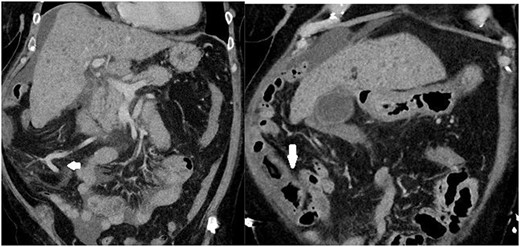

Given initial biochemical markers suggested a significant bleeding diathesis (Hemoglobin 55 g/L(Reference (120–160 g/L).); low platelets (88 × 109/ L)(Reference (150–450 x 109/L).); elevated INR (1.5)(Reference (<1.0).); and normal liver function tests, urea and inflammatory markers), she was taken for a computed tomography (CT)-angiogram of the abdomen and pelvis. A focus of active bleeding on all phases was not found with the radiologist reporting non-specific porta hepatis oedema without any evidence of cirrhosis, intrabdominal ascites, or vascular thrombus (Fig. 1). Despite adequate medical optimisation and blood transfusions the next day she collapsed and deteriorated acutely due to a presumed acute bleed, given her CT head was unremarkable. After intense resuscitation, the patient was taken to theater emergently where the gastroscopic findings were unremarkable and varices were not identified, whereas the colonoscopy found significant severe inflammation, a large adherent blood clot, congestion (oedema) and caecal erythema (Fig. 2). At this time, the radiologist’s report for the liver ultrasound performed immediately before the endoscopic procedures confirmed a new diagnosis of liver cirrhosis. After adequate further medical investigation and optimisation of her liver cirrhosis, an iron transfusion and 3 days of a continuous octreotide infusion, she went home for further outpatient management of her liver disease without any further stigmata of bleeding to date.

Images depicting a single slice of the CT Abdomen/Pelvis with contrast completed on admission. Arrows pointing to subtly dilated mesenteric vessels, as well as thickened bowel affected by PHC, is depicted in Fig. 2.

Instead, this case presents a strong argument for the use of CT from the armamentarium of general surgeons in the diagnosis of PHC because it provided invaluable clues depicted in Fig. 1. Although initially not identified, the radiologists subsequently commented that the mesenteric vessels showed significant venous dilatation without fat stranding to suggest widespread inflammation or infection. Instead, the bowel draining into these vessels displayed a thicker wall suggesting dilatation and possibly venous congestion contributing to the bowel thickening and non-specific inflammation. This evidence of portal hypertension coupled with endoscopic findings led to successful diagnosis and management of PHC before the diagnosis of cirrhosis on ultrasound.